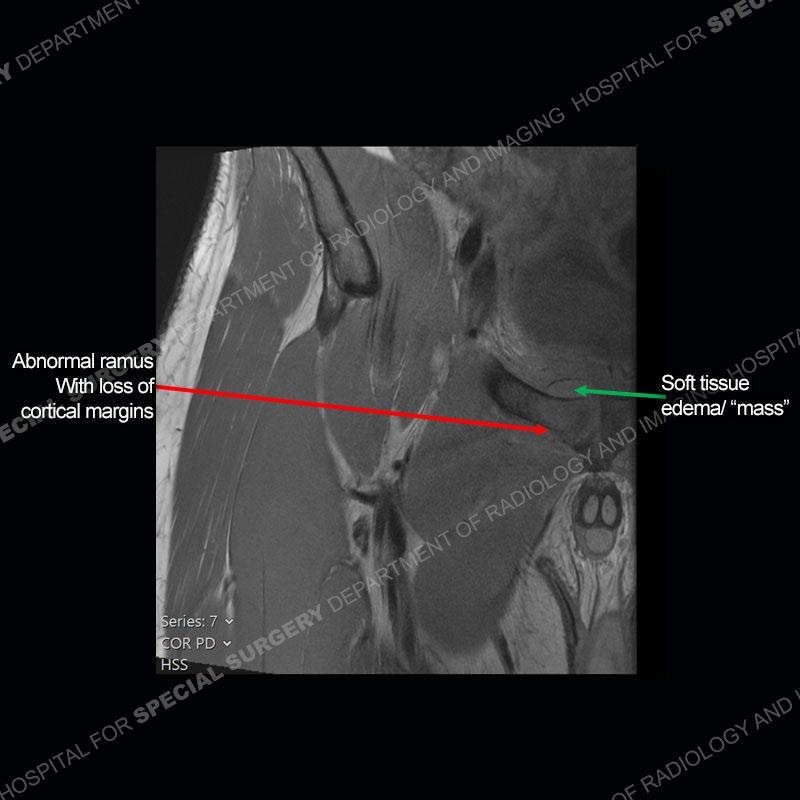

Radiographs did not demonstrate any clear abnormality. The MRI shows markedly abnormal signal of the right superior pubic ramus and abnormal signal/”mass” extending into the adjacent soft tissue. The inferior articular surface of the ramus showed what was thought to be bony destruction. CT examination shows a destructive process of the right superior pubic ramus.

Subsequent MRI in a very short time interval shows markedly increased abnormality of the ramus and increased edema and “mass” of the soft tissue. Post contrast imaging shows multiple, rim enhancing collections of the soft tissue and similar albeit less conspicuous enhancing collection of the ramus.